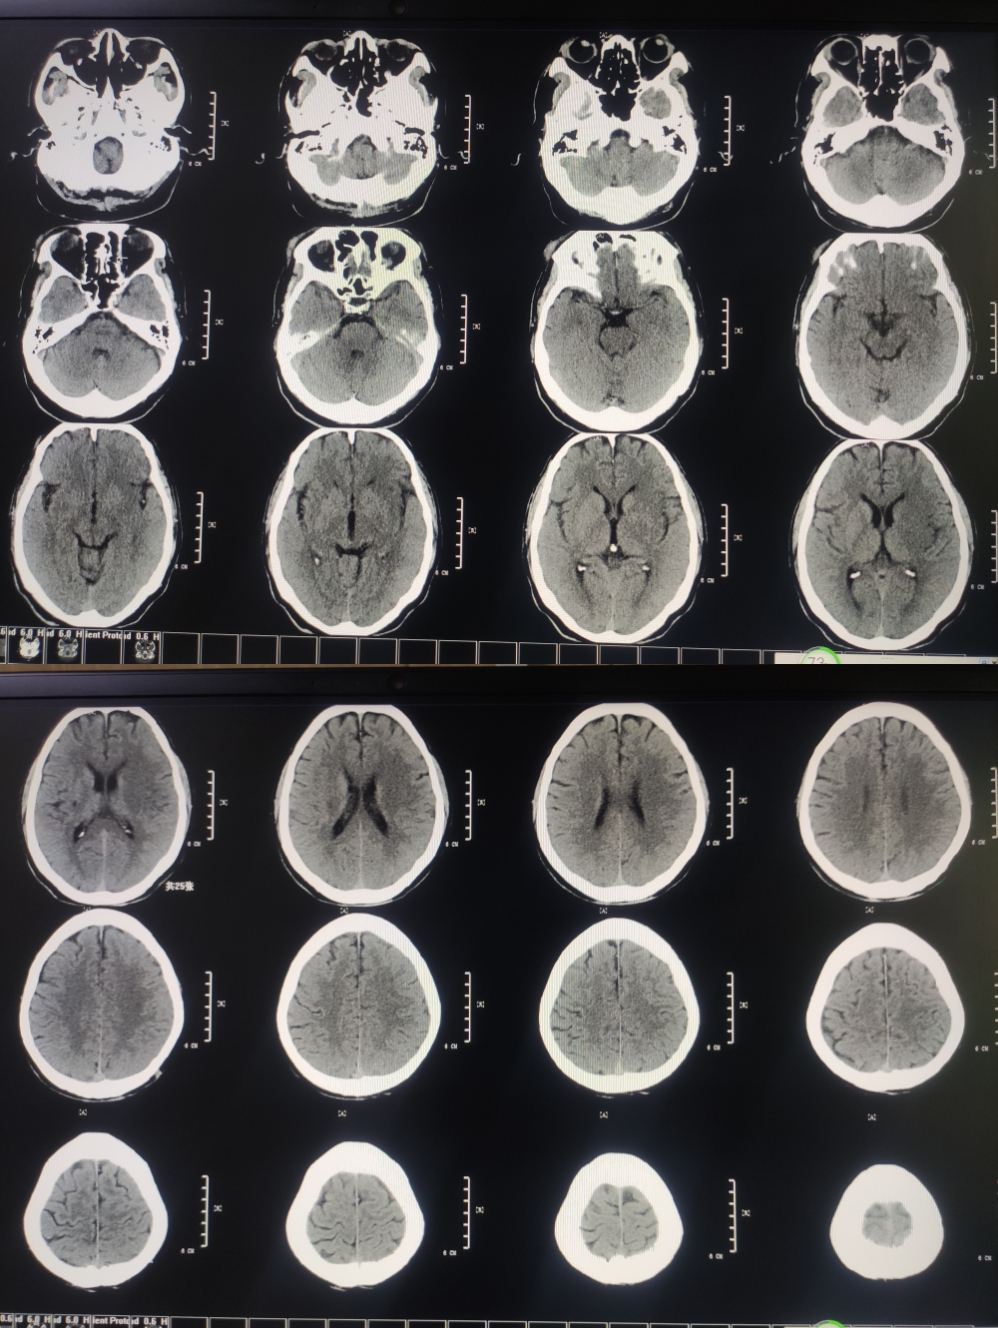

65岁男性,主诉:发现右侧肢体无力,言语不能3小时。NHISS评分:16分,CT-ASPECT评分:5分。

MRA提示:左侧颈内动脉末端及左侧大脑中动脉未见显影。DWI提示左侧大脑中动脉供血区高信号。DWI-Aspect评分:4分。醒后卒中,DWI信号不高,考虑存在大体积缺血半暗带,急诊血管内治疗。

3.术后血管通畅,术前Aspect评分低,最怕高灌注,所以到重症不醒麻醉,脱水,控制血压,降颅内压及对症支持治疗。